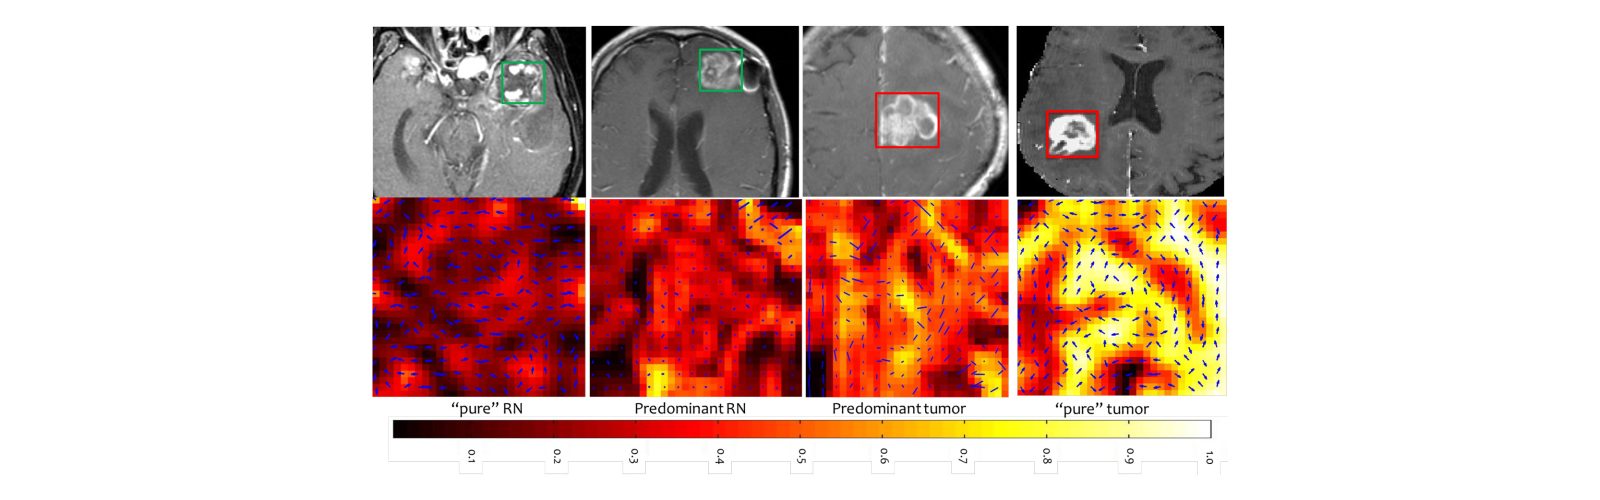

IDiA Lab develops artificial intelligence (AI), machine learning (ML), and statistical modeling approaches for translational applications in oncology and neurological disorders. Our primary focus is on advancing tools for disease prediction, prognosis, and treatment assessment. A key approach of research involves identifying radiomic (image-based) phenotypes from medical imaging and exploring their associations with genomics (radiogenomics) and histopathology (radiopathomics) to enhance disease characterization.